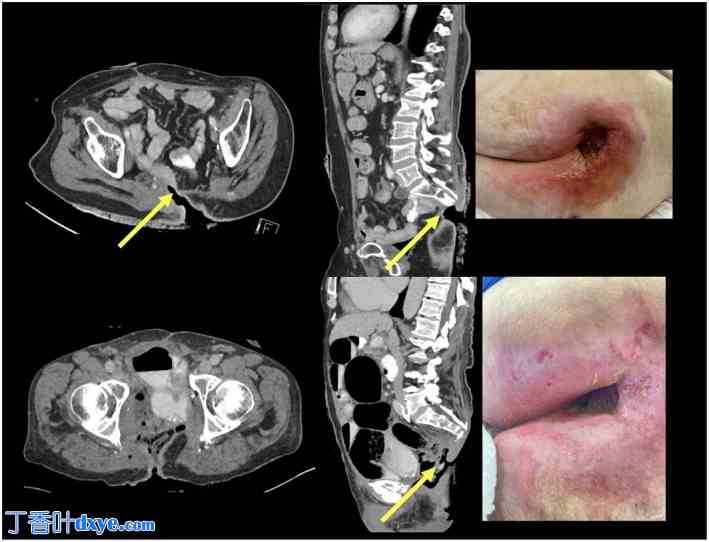

尽管取得了这些进展,但接受 TPE 治疗晚期盆腔恶性肿瘤患者生存率的提高也带来了新的挑战,例如空盆综合征 (EPS) 的出现。空盆综合征(EPS)的特征是脏器廓清术后盆腔内脏缺失,其临床难题复杂,发病率和死亡率显著增加。EPS最难处理的并发症之一是肠会阴瘘(EPF,图1)。随着脏器廓清术后生存率的不断提高,EPS和EPF的发病率及其影响也日益凸显。然而,关于该并发症的最佳治疗策略的数据仍然匮乏。因此,在EPS脏器廓清术后背景下,了解EPF的发病率、预后和治疗模式,对于为这一日益壮大的患者群体提供整体护理至关重要。随着越来越多的机构在这些根治性手术方面积累经验,以及生存结果的改善,解决该患者群体的长期并发症也因此变得更加重要。

图 1.

肠会阴瘘 (EPF) 可导致严重的全身和局部并发症。这些并发症包括严重脓毒症的发生,其特征是全身炎症反应和多器官功能障碍,需要紧急医疗干预。空盆腔内的小肠易发生瘘管(黄色箭头),导致胃肠液通过瘘管流失。这会导致严重的皮肤擦伤和糜烂,造成骶骨皮肤大面积缺损,加剧电解质失衡,并导致严重营养不良,进一步损害生理稳定性。由此导致的身体虚弱通常最终导致严重的活动能力丧失。此外,EPF 的慢性和致残性给患者带来了巨大的心理负担,表现为严重的精神痛苦、焦虑和抑郁,从而大大降低了他们的生活质量。